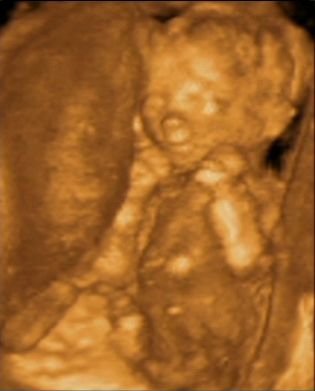

Én az altatást választottam, amiért az aneszteziológus doki kétszer is megdorgált, hogy a spinális jobb lett volna (gondolom azért, mert altatáskor nagyon kell sietni a dokinak). Az én orvosom nagyon gyors és ügyes volt, és azzal együtt, hogy 9-kor toltak ki a szülőszobából, lift, majd a fenti mindenféle előkészületeket is hozzáadva 9.26-kor már megszületett az én drága kis Hannám, aki most itt fekszik a kiságyban.